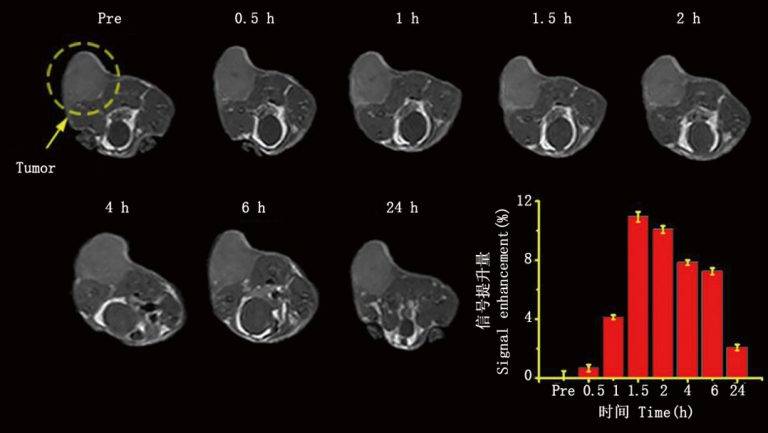

皮下肿瘤成像